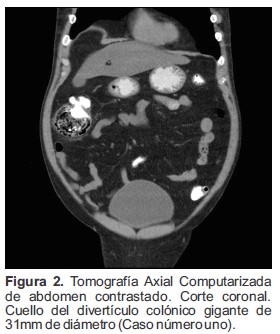

Se realizó Tomografía Axial Computarizada (TAC) de abdomen contrastado en donde se visualizó una dilatación sacular en la región del ángulo hepático del colon ascendente la cual midió 7.0 cm de diámetro antero posterior, 5.5 cm longitud y 6.2 cm transverso. Esta lesión se encontraba ocupada casi en su totalidad por materia fecal (Figura 1) y presentaba un cuello de 31.0 mm de diámetro (Figura 2 y 3), hallazgo compatible con divertículo gigante del colon, además, presentaba ligero engrosamiento de la pared y de la grasa circundante, sin embargo, no se observó gas libre en el abdomen.

Figura 2. Tomografía Axial Computarizada de abdomen contrastado. Corte coronal. Cuello del divertículo colónico gigante de 31mm de diámetro (Caso número uno).